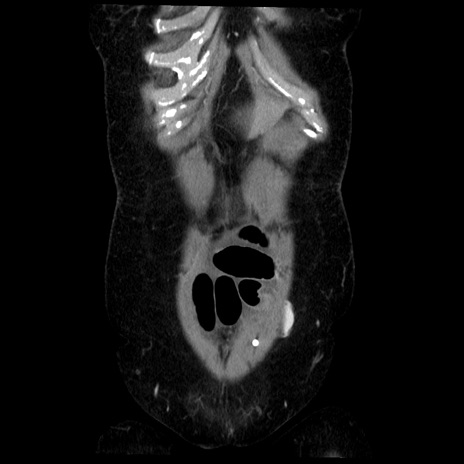

症例6(冠状断像)

【症例】50歳代女性

【主訴】下腹部痛

【現病歴】本日朝より下痢2回あり。 昼食を食べた後、嘔吐3回、下腹部痛認め、症状軽快せず、当院救急搬送。

最終食事:本日昼(生ものなし)。 昨日の夜、刺身を食ぺたとのこと。周囲に同様の症状の者なし。普段、排便は毎日あるとのこと。

【既往歴】卵巣癌術後(8年前に当院で卵巣摘出)

【身体所見】 意識清明、腹部:平坦、腸蠕動音→、やや硬、下腹部自発痛・圧痛あり、反跳痛あり、筋性防御なし。

【データ】WBC 16000、CRP 0.01